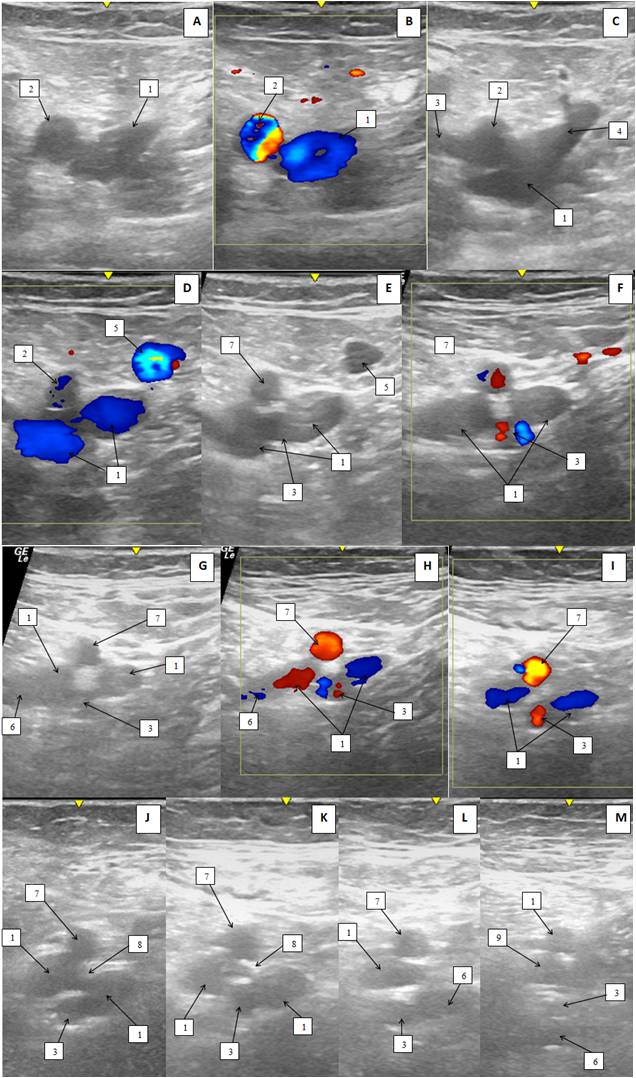

Справа: ГАБ представлена двумя стволами, которые отходят от латеральной и задней поверхностей ОБА. ОБВ выше уровня СФС представлена одним стволом, ниже уровня СФС представлена двумя стволами, расположенными между одним из стволов ГАБ, который отходит от задней поверхности ОБА. В латеральный ствол ОБВ впадает ГВБ. На уровне впадения ГВБ, медиальный и латеральный ствол ОБВ соединяются между собой коммуникантной ветвью. Дистальнее этого уровня медиальный ствол ОБВ сопровождает ГАБ, отходящую от задней поверхности ОБА. Латеральный ствол ОБВ сопровождает ПБА (рис. 3, 4).

Рис. 3. Ультразвуковая дуплексная сканограмма сосудов верхней трети бедра справа пациентки К. (двухмерный, серошкальный режим (В-режим) и режим цветового допплеровского картирования; поперечный срез): А–Б — выше уровня сафенофеморального соустья; В — уровень сафенофеморального соустья; Г–Н — ниже уровня сафенофеморального соустья.

Примечания: 1 — общая бедренная вена, 2 — общая бедренная артерия, 3 — глубокая артерия бедра, 4 — сафенофеморальное соустье, 5 — большая подкожная вена, 6 — глубокая вена бедра, 7 — поверхностная бедренная артерия, 8 — анастомоз между общей бедренной веной, 9 — бедренная вена.